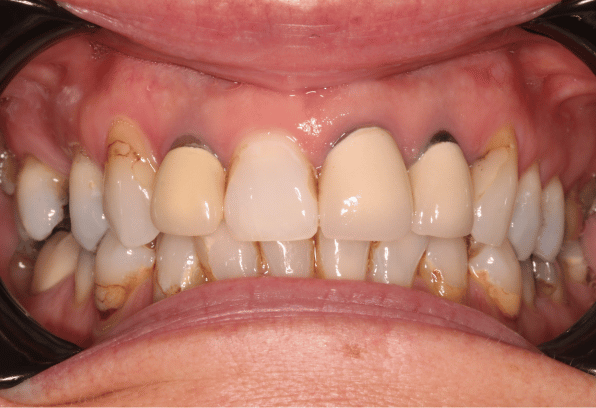

After

After

This smile makeover includes composite bonding, ceramic crowns and a veneer to enhance our patient's smile.